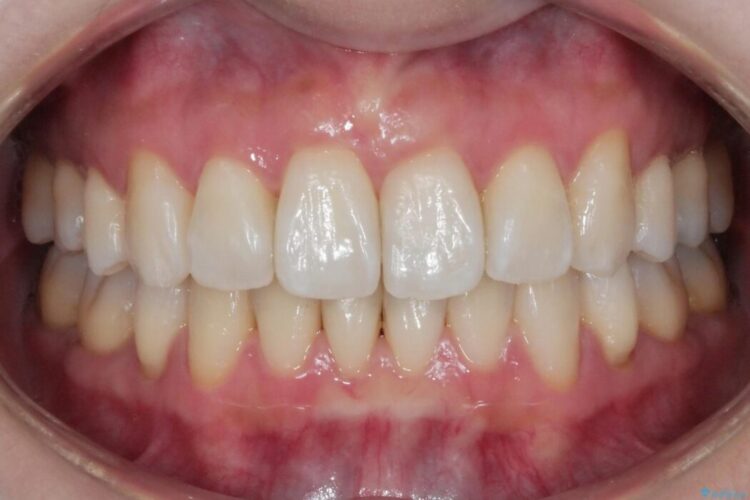

抜歯矯正後の上の前歯の後戻りが気になるとご来院された患者様です。

インビザラインモデレートで治療が可能と診断し、矯正治療を行いました。

歯と歯の間を削るのと、歯列のU字型のアーチを僅かに外側に広げる事でスペースを作り、前歯の角度の改善をしました。

保定装置は、マウスピースと前歯の裏側を細いワイヤーで固定(ボンディングリテーナー)を併用していただいてます。